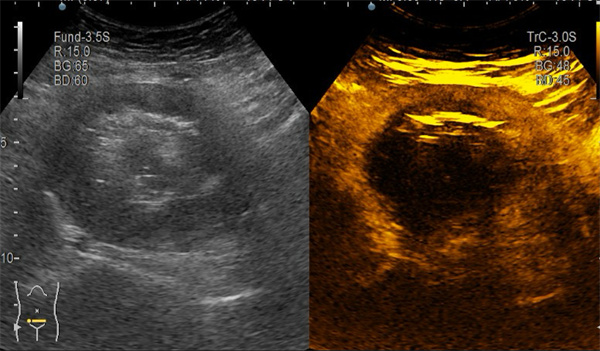

消融前,造影剂可以流入肌瘤内部,肌瘤被“点亮”

消融后,造影剂不再能流入,肌瘤呈“黑洞”